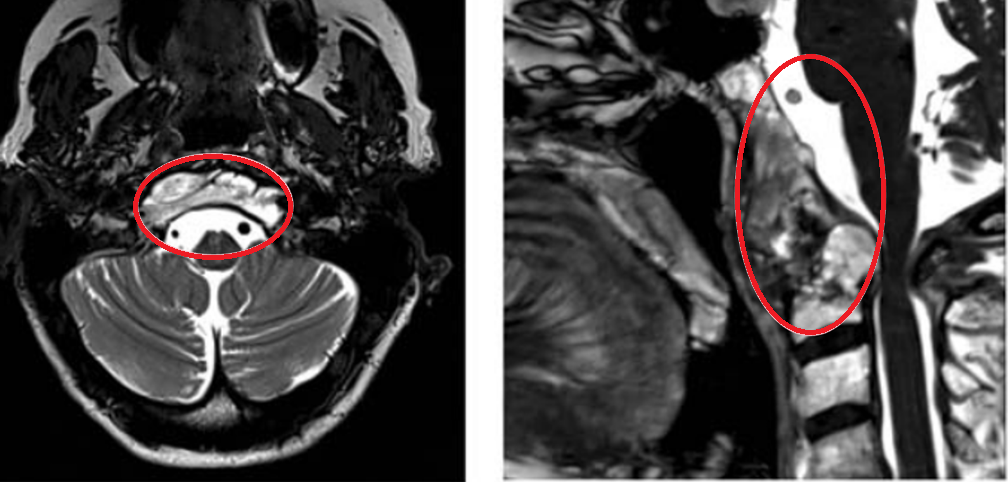

▼图a-b:术前MR显示颅颈交界区巨大脊索瘤,尺寸51.3×74.3×25.9mm,呈浸润性生长。

▼图c-d:脊索瘤向周边浸润,下至C5-C6水平。